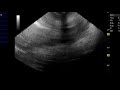

ОДЫШКА И УДУШЬЕ

Чувство нехватки воздуха?

Чувство неполного вдоха. Не хватает воздуха